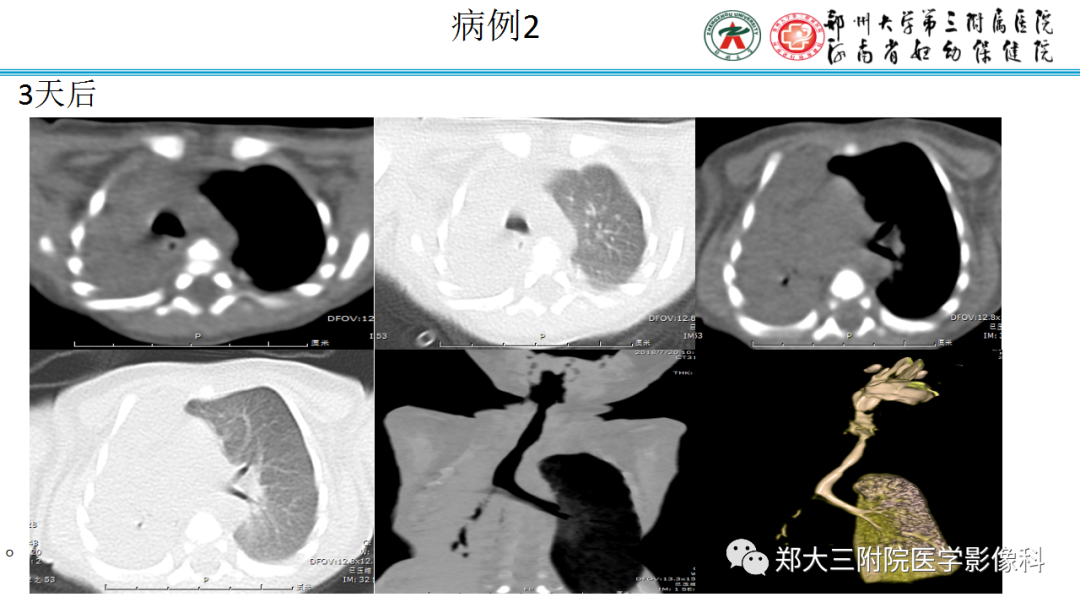

▲病例2:肝母细胞瘤。图1:CT平扫肝左右叶肿块,呈低密度,内部密度不均。图2肝内可见钙化灶。图3增强扫描肝内病灶不均匀明显强化,片状或结节状强化,见假包膜结构,图4可见肝内转移灶。